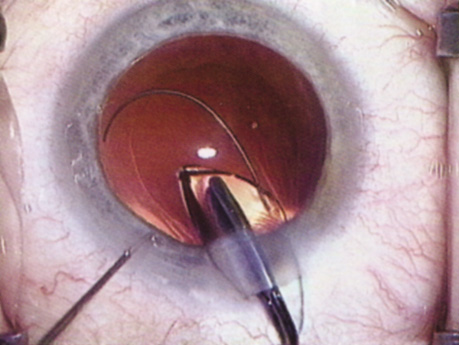

Fig. 11. A crisp “golden ring” is seen from the fluid cleft between the epinucleus and nucleus with hydrodelineation.

Hydrodissection can be performed after the surgeon has successfully completed capsulorrhexis.97 If the capsulorrhexis is not intact, fluid forced around the interior of the capsule may cause the bag to splay open. With capsulorrhexis, hydrodissection is a safe and extremely useful maneuver. Hydrodissection can be thought of as two maneuvers: hydrodelineation and cortical cleaving hydrodissection. By placing a 27-gauge cannula on a syringe filled with balanced saline solution (BSS), the surgeon can direct fluid beneath the residual anterior capsular rim to create a cleavage plane. Depending on the direction the fluid wave takes, different lamellae of the cataract will be separated. Hydrodelineation is the term used when the cleavage plane separates the adult nucleus from the fetal nucleus or the adult nucleus from the more peripheral epinucleus. Hydrodelineation often results in the characteristic golden ring sign (Fig. 11). Cortical cleavage occurs when the cortex is separated from the capsular bag (Fig. 12). Finding the cortical cleavage plane may be facilitated by gently lifting the capsular margin away from the cortex with the BSS cannula before injecting. Several small bursts of fluid allow the surgeon to monitor progress of the fluid wave. When dealing with a soft nucleus, the authors strive to perform true cortical cleaving hydrodissection. For a hard nucleus, hydrodelineation allows manipulation of less of the nuclear bulk, although the remaining epinuclear shell must be addressed in an additional step. Hydrodelineation is particularly useful if the nucleus is not freely mobile after cortical cleaving hydrodissection.